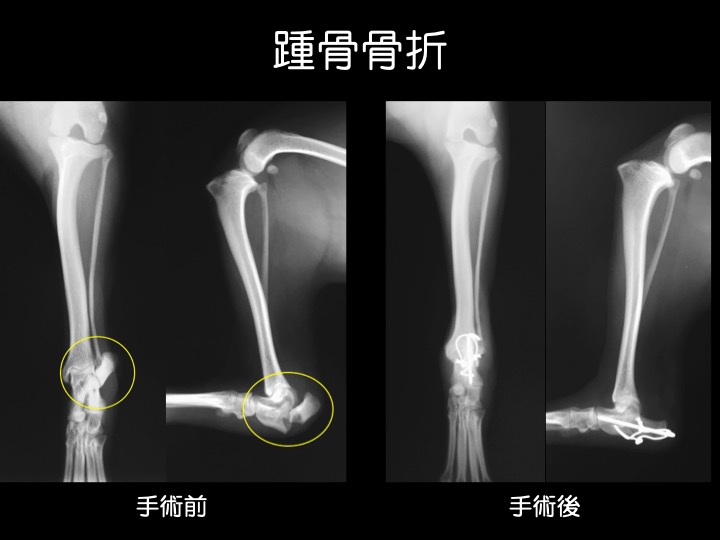

・脛骨すなわち「スネ(脛)」の周囲は筋肉などが薄く血流に乏しいため、この箇所の骨折は癒合不全が起こりやすいと言われています。

・写真のような、体の外に装具がついた固定具を「創外固定」と呼びます。骨の癒合にあわせて段階的に外していき、最終的には全て外して完治となります。